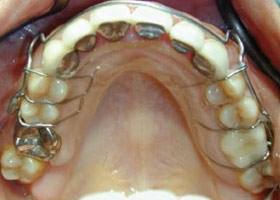

4. 使用活動式矯正裝置矯正中(矯正方式因人而異)。